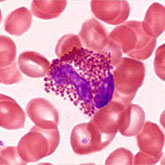

Histology is the study of the microanatomy of cells, tissues, and organs as seen through a microscope. It examines the correlation between structure and function.

Histology Guide teaches the visual art of recognizing the structure of cells and tissues and understanding how this is determined by their function. Rather than reproducing information found in a histology textbook, a user is shown how to apply this knowledge to interpret cells and tissues as viewed through a microscope.

Because of the high cost of purchasing (and maintaining) microscopes and preparing (or purchasing) slide collections, histology is often taught today without laboratories. A histology atlas is frequently used as a replacement. This is unfortunate because no matter how good the few images in a textbook or histology atlas are, they cannot replace the experience of viewing a specimen through a microscope.

Histology Guide solves this problem by recreating the look and feel of a microscope in an intuitive, browser-based interface.

An Aperio slide scanner was used to obtain a high-resolution image of each slide in its entirety. Large tissues are up to 34 GB for a single, uncompressed image of 150,000 x 75,000 pixels.

The contrast, color, and sharpness of each image were adjusted to at least maintain the appearance of the tissue as seen through a microscope. In many cases, these adjustments improved upon their visual appearance.

Unlike low-resolution images, users can interactively explore these large images by zooming-and-panning in real-time. A software-based virtual microscope (Zoomify HTML5 Enterprise) allows the examination of large and small structures in the same specimen.

This approach provides a more engaging learning experience and sense of scale, proportion and context that is not possible with a traditional histology textbook or atlas.

The Atlas of Human Histology: A Guide to Microscopic Structure of Cells, Tissues and Organs by Robert L. Sorenson and T. Clark Brelje provides a print version of the core slides from this website. Individual slides are presented as a series of images of increasing magnification to help convey a sense of scale and proportion. This atlas allows each student to have an easily accessible, printed summary of the essential slides from this website.